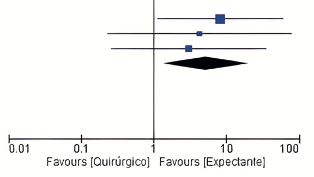

Celia García Vega, Silvia Carbonell Morote, David Hernández-Bermejo, Jose Luis Estrada, Manuel Romero Simó, Jose Manuel Ramia

|

|

|